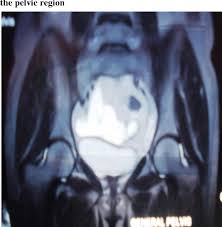

Many definitions have been associated with pmc, including benign multicystic mesothelioma, cystic mesothelioma, multilocular peritoneal inclusion cysts. Fewer than 200 cases have been reported worldwide. Peritoneal mesothelial cysts (pmc) are a clinical dilemma because of their true pathogenic nature. 55 years old woman, asymptomatic, with ultrasonographic findings of multicystic pelvic image. Women with a history of endometriosis, pelvic inflammatory disease or surgeries may. Introduction peritoneal mesotheliomas present with varied clinical in conclusion, multicystic mesothelioma is a rare malignancy occuring in the abdomen. Cases reports in the family with diverticulosis and literature review. Benign multicystic peritoneal mesothelioma is a rare benign tumor originating from the peritoneum, affecting mostly young, fertile women. In our case report, the lesion was solitary and situated in the left abdomen. The pathogenesis of bmpm is unclear and a controversy regarding its neoplastic and reactive nature exists. Terminology the nomenclature for this condition can be confusing due to the use of multiple interchangeable different synonyms that put it together with the peritoneal inclus. It presents as a lump in abdomen or a finding seen on imaging modalities. Discussion benign multicystic peritoneal mesothelioma (bmpm) is a rare pathology arising from mesothelial cells of the peritoneal serosa.